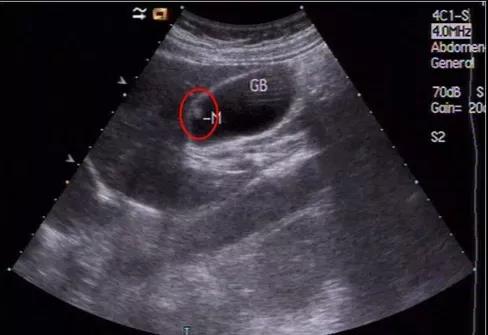

(▲膽囊假性息肉)

所以不是所有的息肉都是真的,假性息肉和癌沒啥關(guān)系,真正要關(guān)注的是:真性息肉!

(▲膽囊真性息肉)